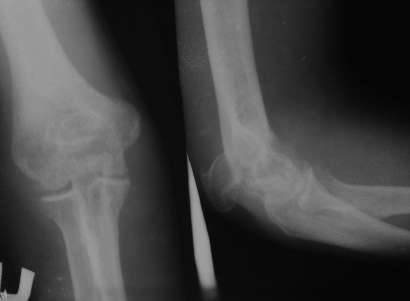

[Ortho] Perelom loktegovo otrоstka

Bolnoy 4 mesyatsa nazad paluchil travmu.

Za meditsinskoy pomotschyu ne obratilsya. Cherez 4 mesyatsa

gospitalizirovan dlya operatsiyi. Moy plan nalojit apparat Ilizarova  s

pastepennoy kompressiyey v oblasti pereloma.

Атамурадов Латиф

Бухарская областная болъница